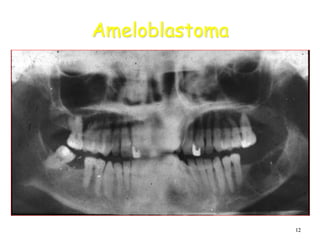

Ameloblastoma (Cont.)

• Most often a well-corticated multilocular

radiolucency.

• “Honey-comb”, “soap-bubble” or “tennis-racket”

appearance.

• May be a well-corticated unilocular lesion

Ameloblastoma

Large multilocular soap bubble appearance.

Typically located in the molar region, angle of the

mandible and ascending ramus

Thin not penetrated cortical plate.

Impacted or neighboring teeth are displaced with

roots often resorped.